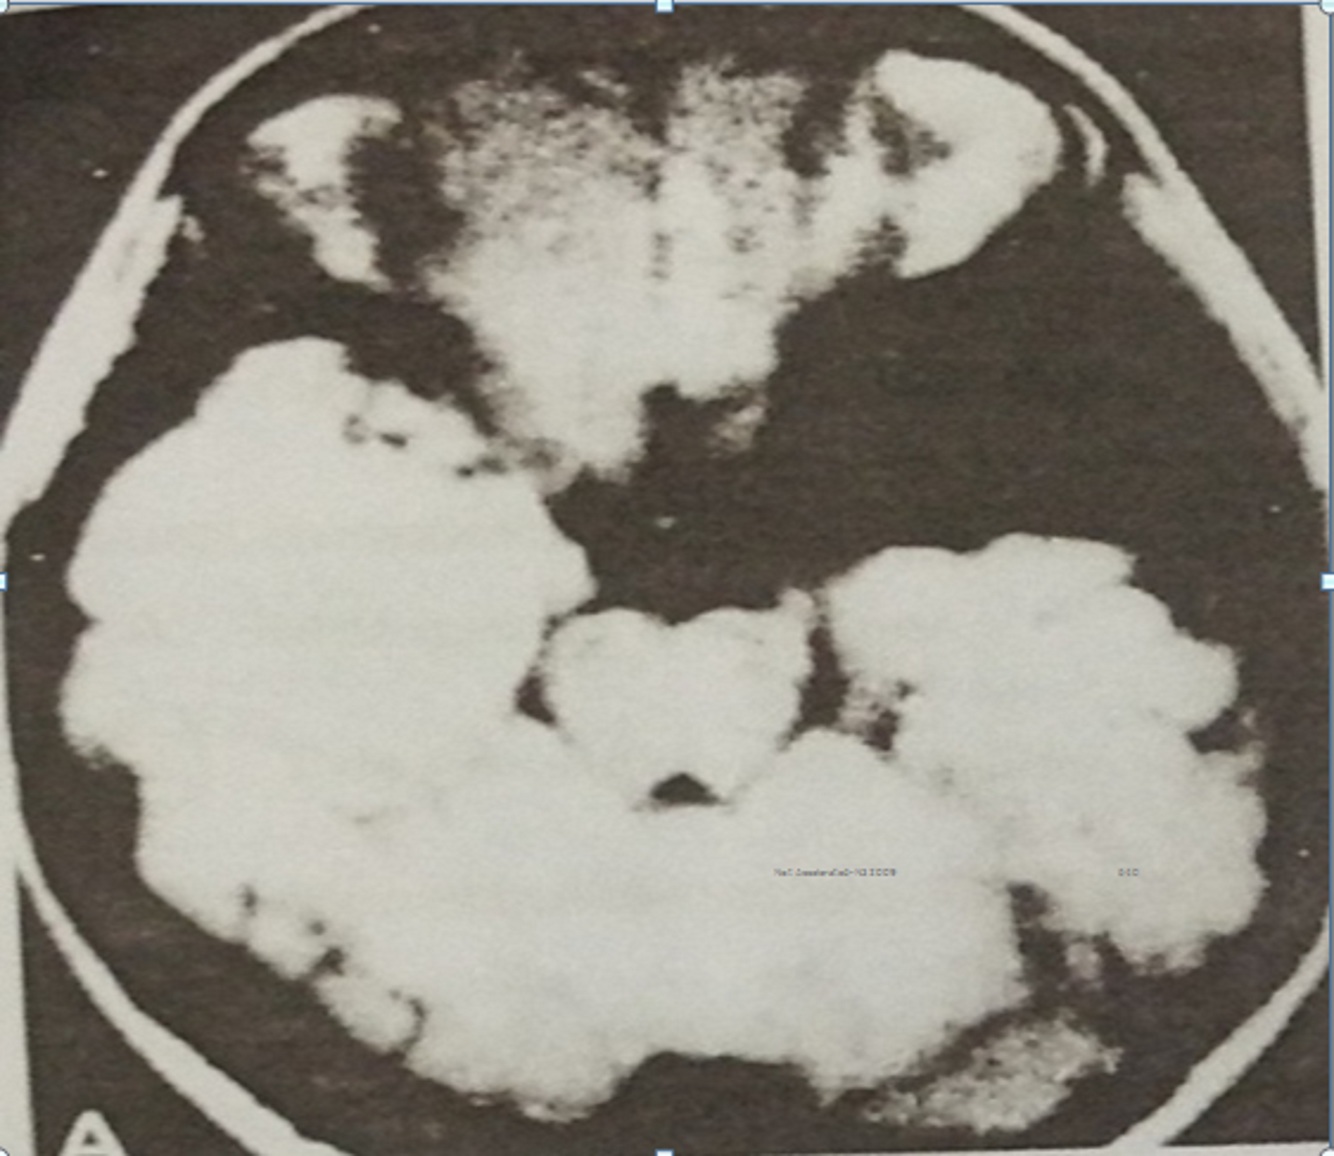

Seorang anak laki-laki 12 tahun menunjukkan riwayat sakit kepala general selama 6 bulan dan 3 bulan riwayat episode unrespon. Episode ini seringkali didahului oleh rasa kecemasandan berlangsung beberapa menit setiap kejadian. Pemeriksaan neurologis normal. MRI ditunjukkan figure 8A telah didapatkan. Manakah pernyataan dibawah ini yang benar ?

A.Cyst pritoneal shunting bukan merupakan terapi yang tepat

B.Abnormalitas primer adalah kegagalan perkembangan lobus temporal

C.Diagnosa yang paling tepat adalah kista arachnoid

D.Craniotomy untuk menghilangkan massa secara lengkap dan fokus epilepsi merupakan indikasi

E.Diagnosa yang paling tepat adalah tumor epidermoid

C